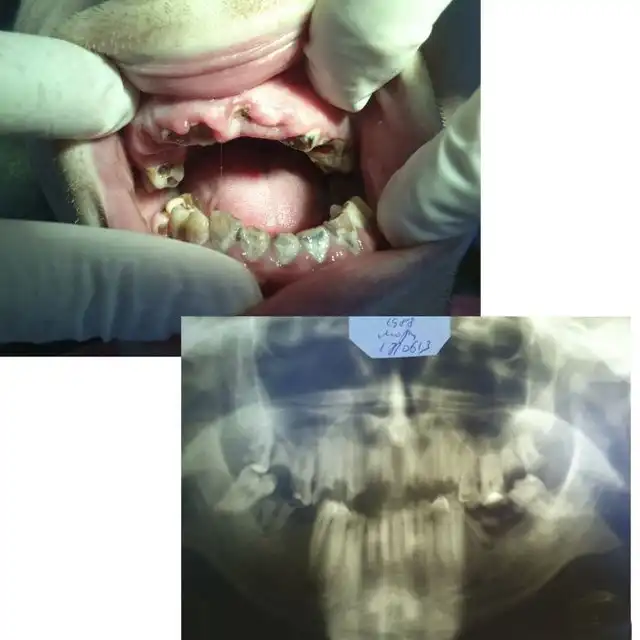

Угадайте, а сколько лет этому пациенту? По понятным причинам я не фотографировал его лицо полностью… Изначально он обращался около двух месяцев назад с переломом нижней челюсти в области суставного отростка слева, и шины наложить ему не могли, т.к. зубов целых почти нет… Был направлен в областную больницу, где походил с пращевидной бинтовой повязкой, и был отпущен домой… Остеосинтеза никто ему не делал. А потом спустя месяца два попал ко мне, после того как у себя на работе упал и ударился тем же местом)))) Очень «правдоподобно»… Но не в этом суть, парню 25 лет!!! Считает, что зубы разрушены, т.к. он на вредном производстве на заводе работает. Но гораздо более вероятная причина — нежелание чистить зубы. На фотографии видно, сколько там налета. И так многие выдумывают самые невероятные причины: работа с кислотой, жизнь в тайге, дальние плаванья, утрата зубов за один месяц после родов и т.п. Все это может повлиять в какой-то степени, но на деле у всех этих пациентов ужасная гигиена и последнее посещение стоматолога при царе Грохе. А у нашего парня зато татуха на всю правую руку, и на то, чтоб ее сделать, он нашел и время, и деньги, и желание… Это наш менталитет… Ездить на дорогой машине, понаделать татух, пирсинг, ходить в дорогих шмотках, но при этом с грязными ушами и нечищеными зубами. Редко кто на приеме попадается с таким уровнем гигиены, чтоб можно было стоматологическое вмешательство проводить. Да-да, есть индекс гигиены специальный, и если он выше определенной величины, то удалять нельзя. Но на деле удаляю, т.к. если строго подходить, то принять можно будет 2-3 человек за смену, остальных отправлять чистить зубы… Но потом люди приходят и с удивлением спрашивают, почему лунка после удаления болит? Никому даже в голову не приходит, что одной из вероятных причин может быть помойка во рту… Так что, друзья, идете к стоматологу — почистите зубы хорошенько ( да и вообще их чистить надо)), даже этой мелочью вы обеспечите себе хорошее отношение врача, потому что чистый рот — большая редкость и приятная неожиданность для стоматолога( к сожалению).

А это его панорамная рентгенограмма. То, что обвел красным, надо удалять. В 25 лет этому парню надо ставить съемные пластиночные протезы. Это такие, как вы видели у своих бабушек и дедушек в стаканах на тумбочке у кровати…